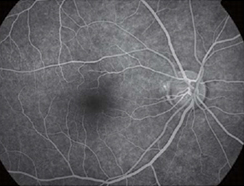

正常 -

フルオレセインという蛍光色素の入った造影剤を腕の静脈から注入し、眼底カメラで網膜の血管を観察します。

血管の形状、血管からの漏出、網膜の虚血などがわかります。